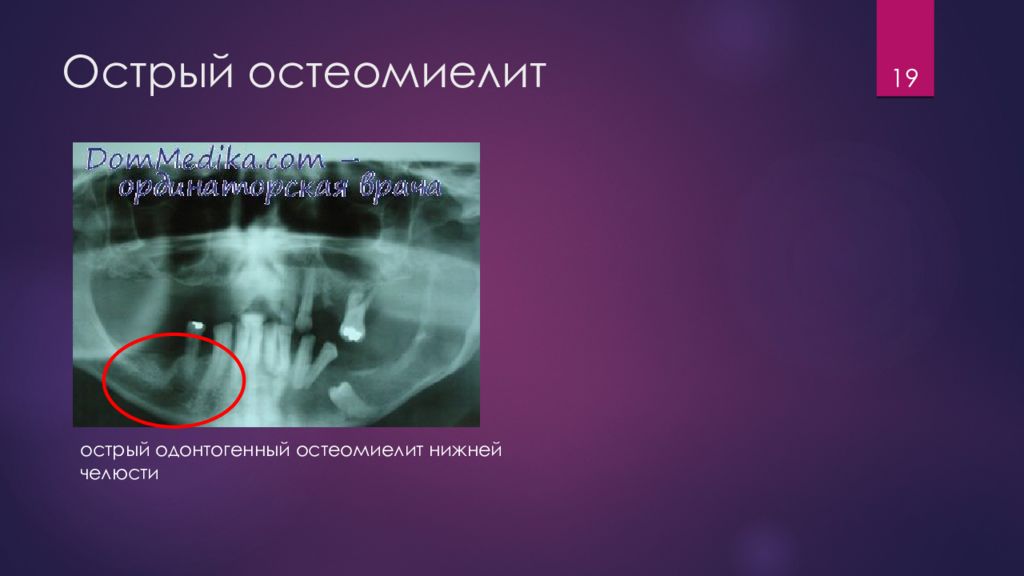

Рентгеновские снимки посттравматического остеомиелита челюсти: Медицинские случаи

Раздел: Образы вокруг